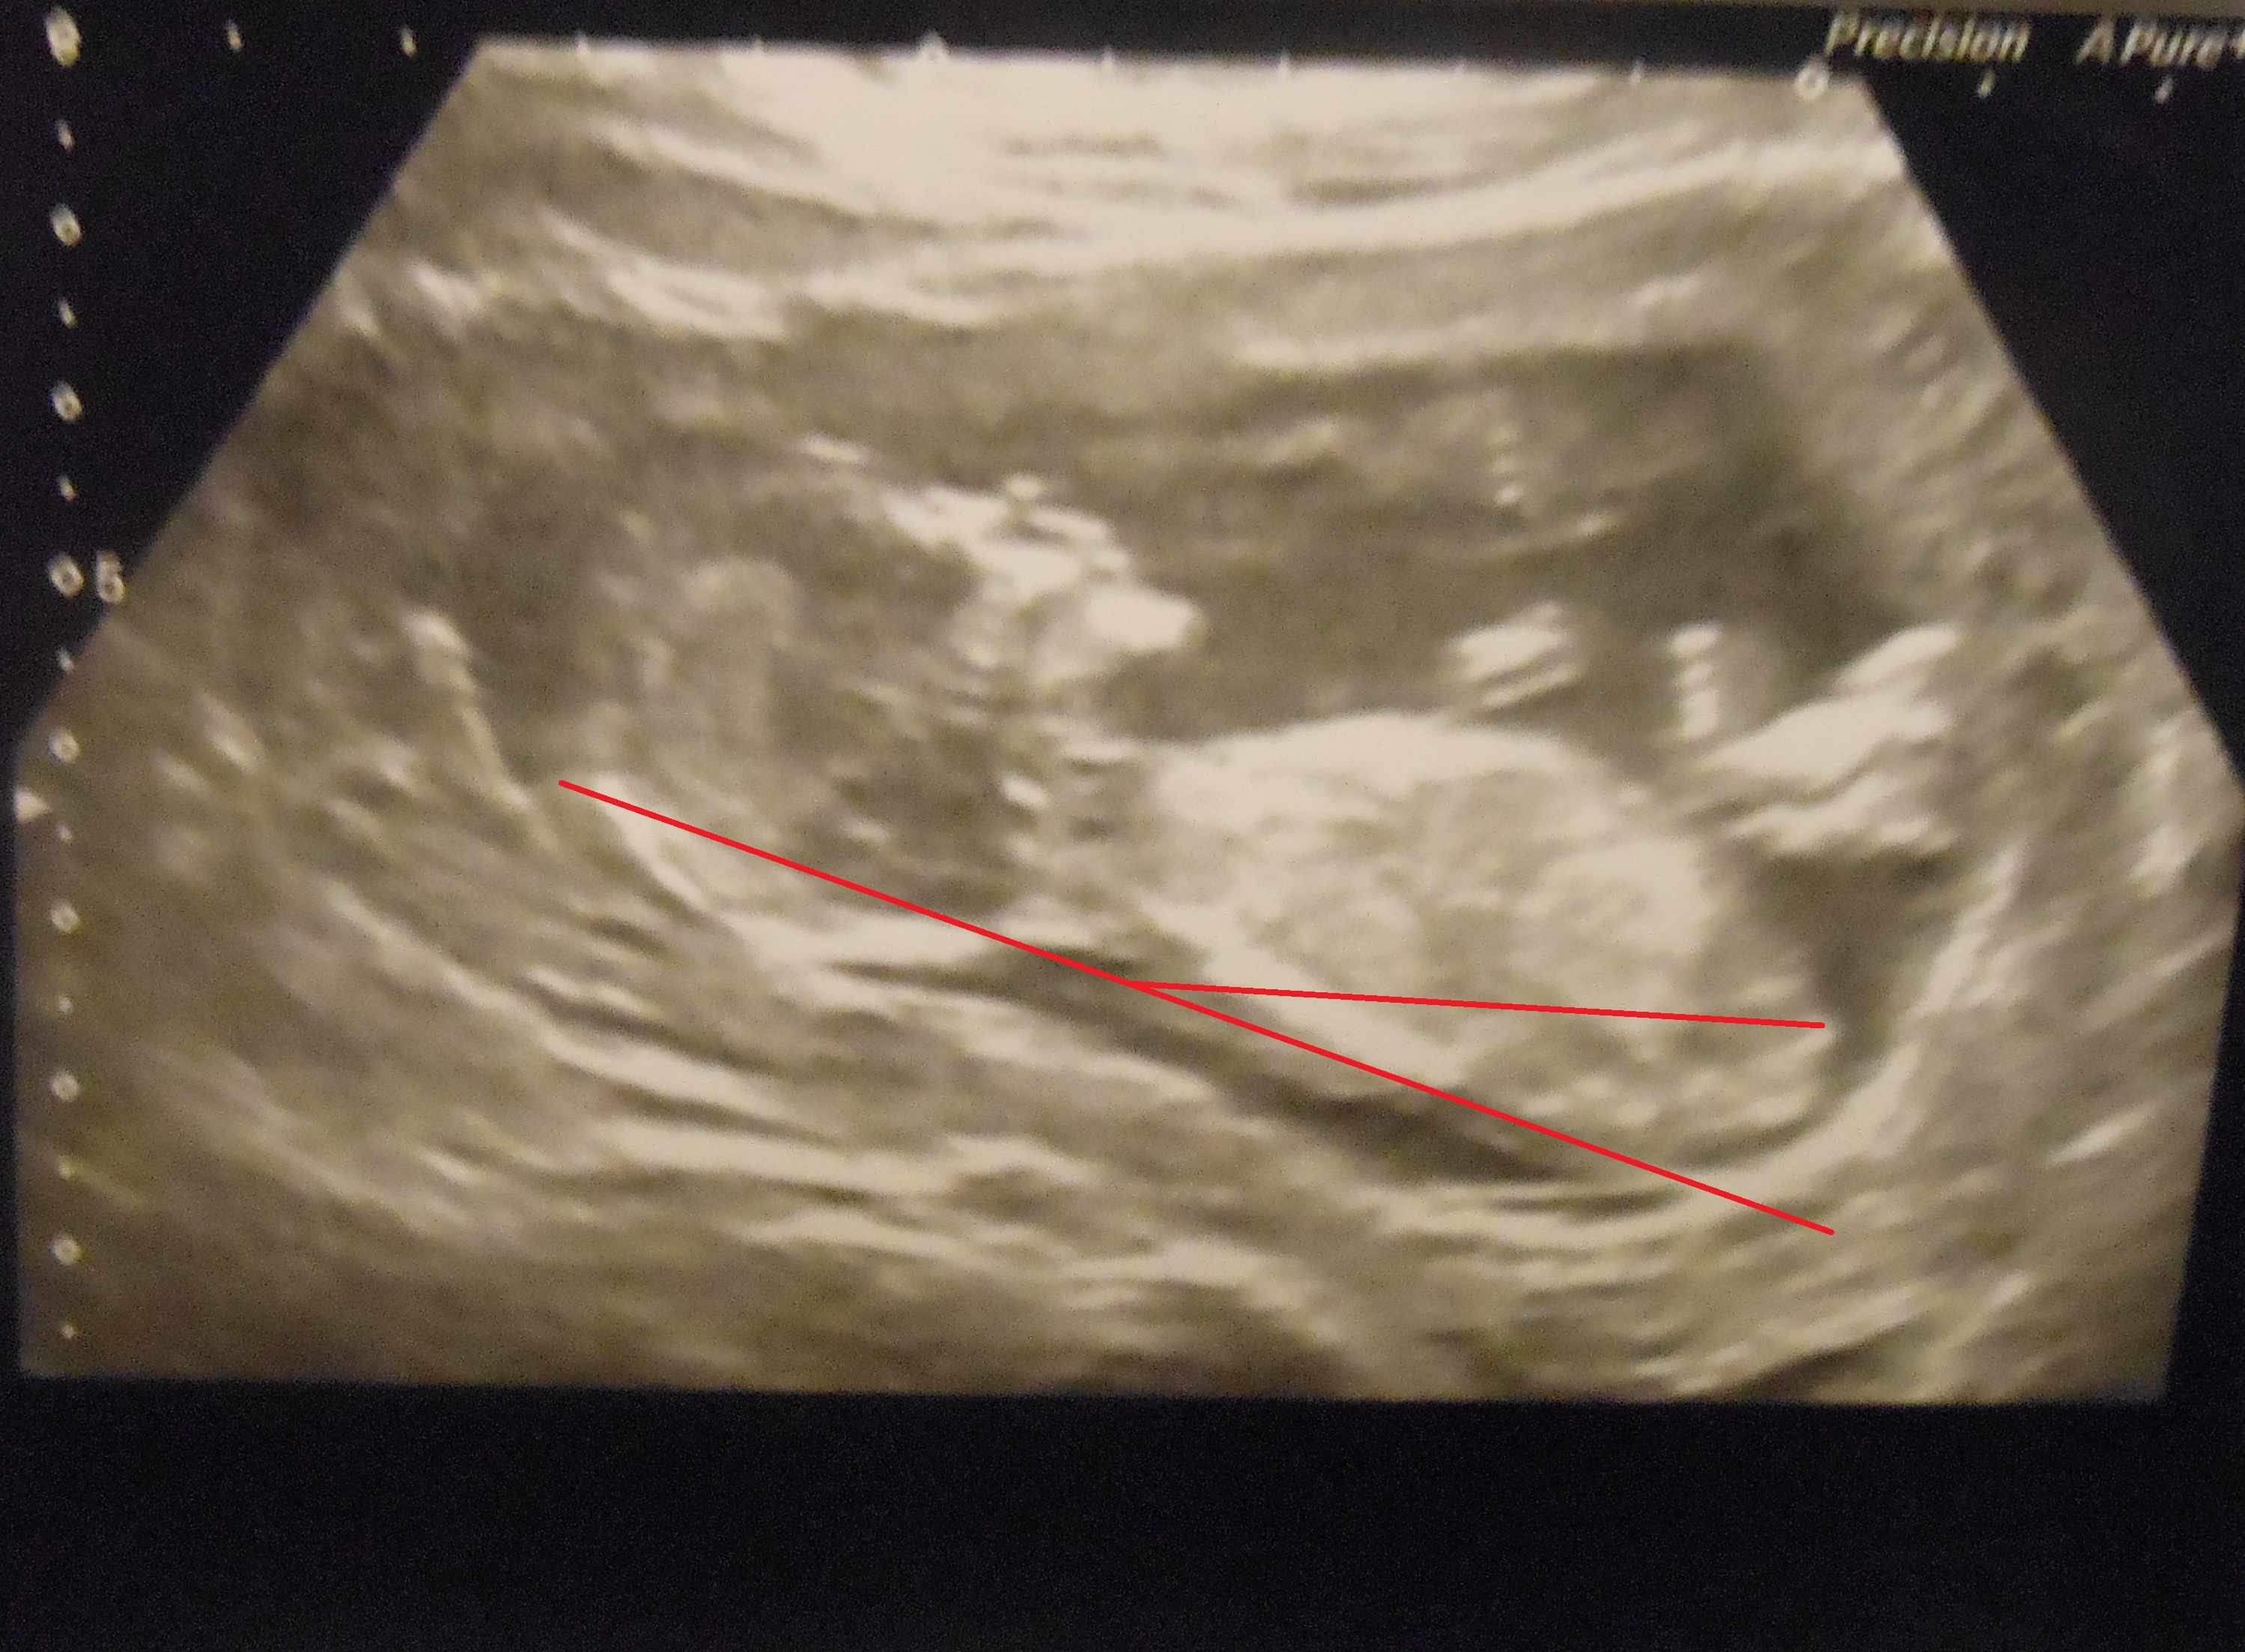

I can't work out which is the right way to look at the nub. This was taken when baby was 13 weeks + 4. My SIL thinks it looks like a girl (so did I originally) and says she has rarely been wrong and guessed her babies and her friends correctly. However when I posted on my birthclub on baby centre all replies said boy! I just want to know what you guys think and what your opinion is as it's totally driving me mad. Any expert eyes and replies are greatly appreciated :)

Attachment 23778Attachment 23779Attachment 23780